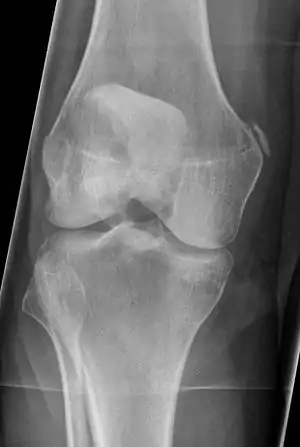

| Pellegrini-Stieda syndrome. Also visible is a fracture of the patella. |